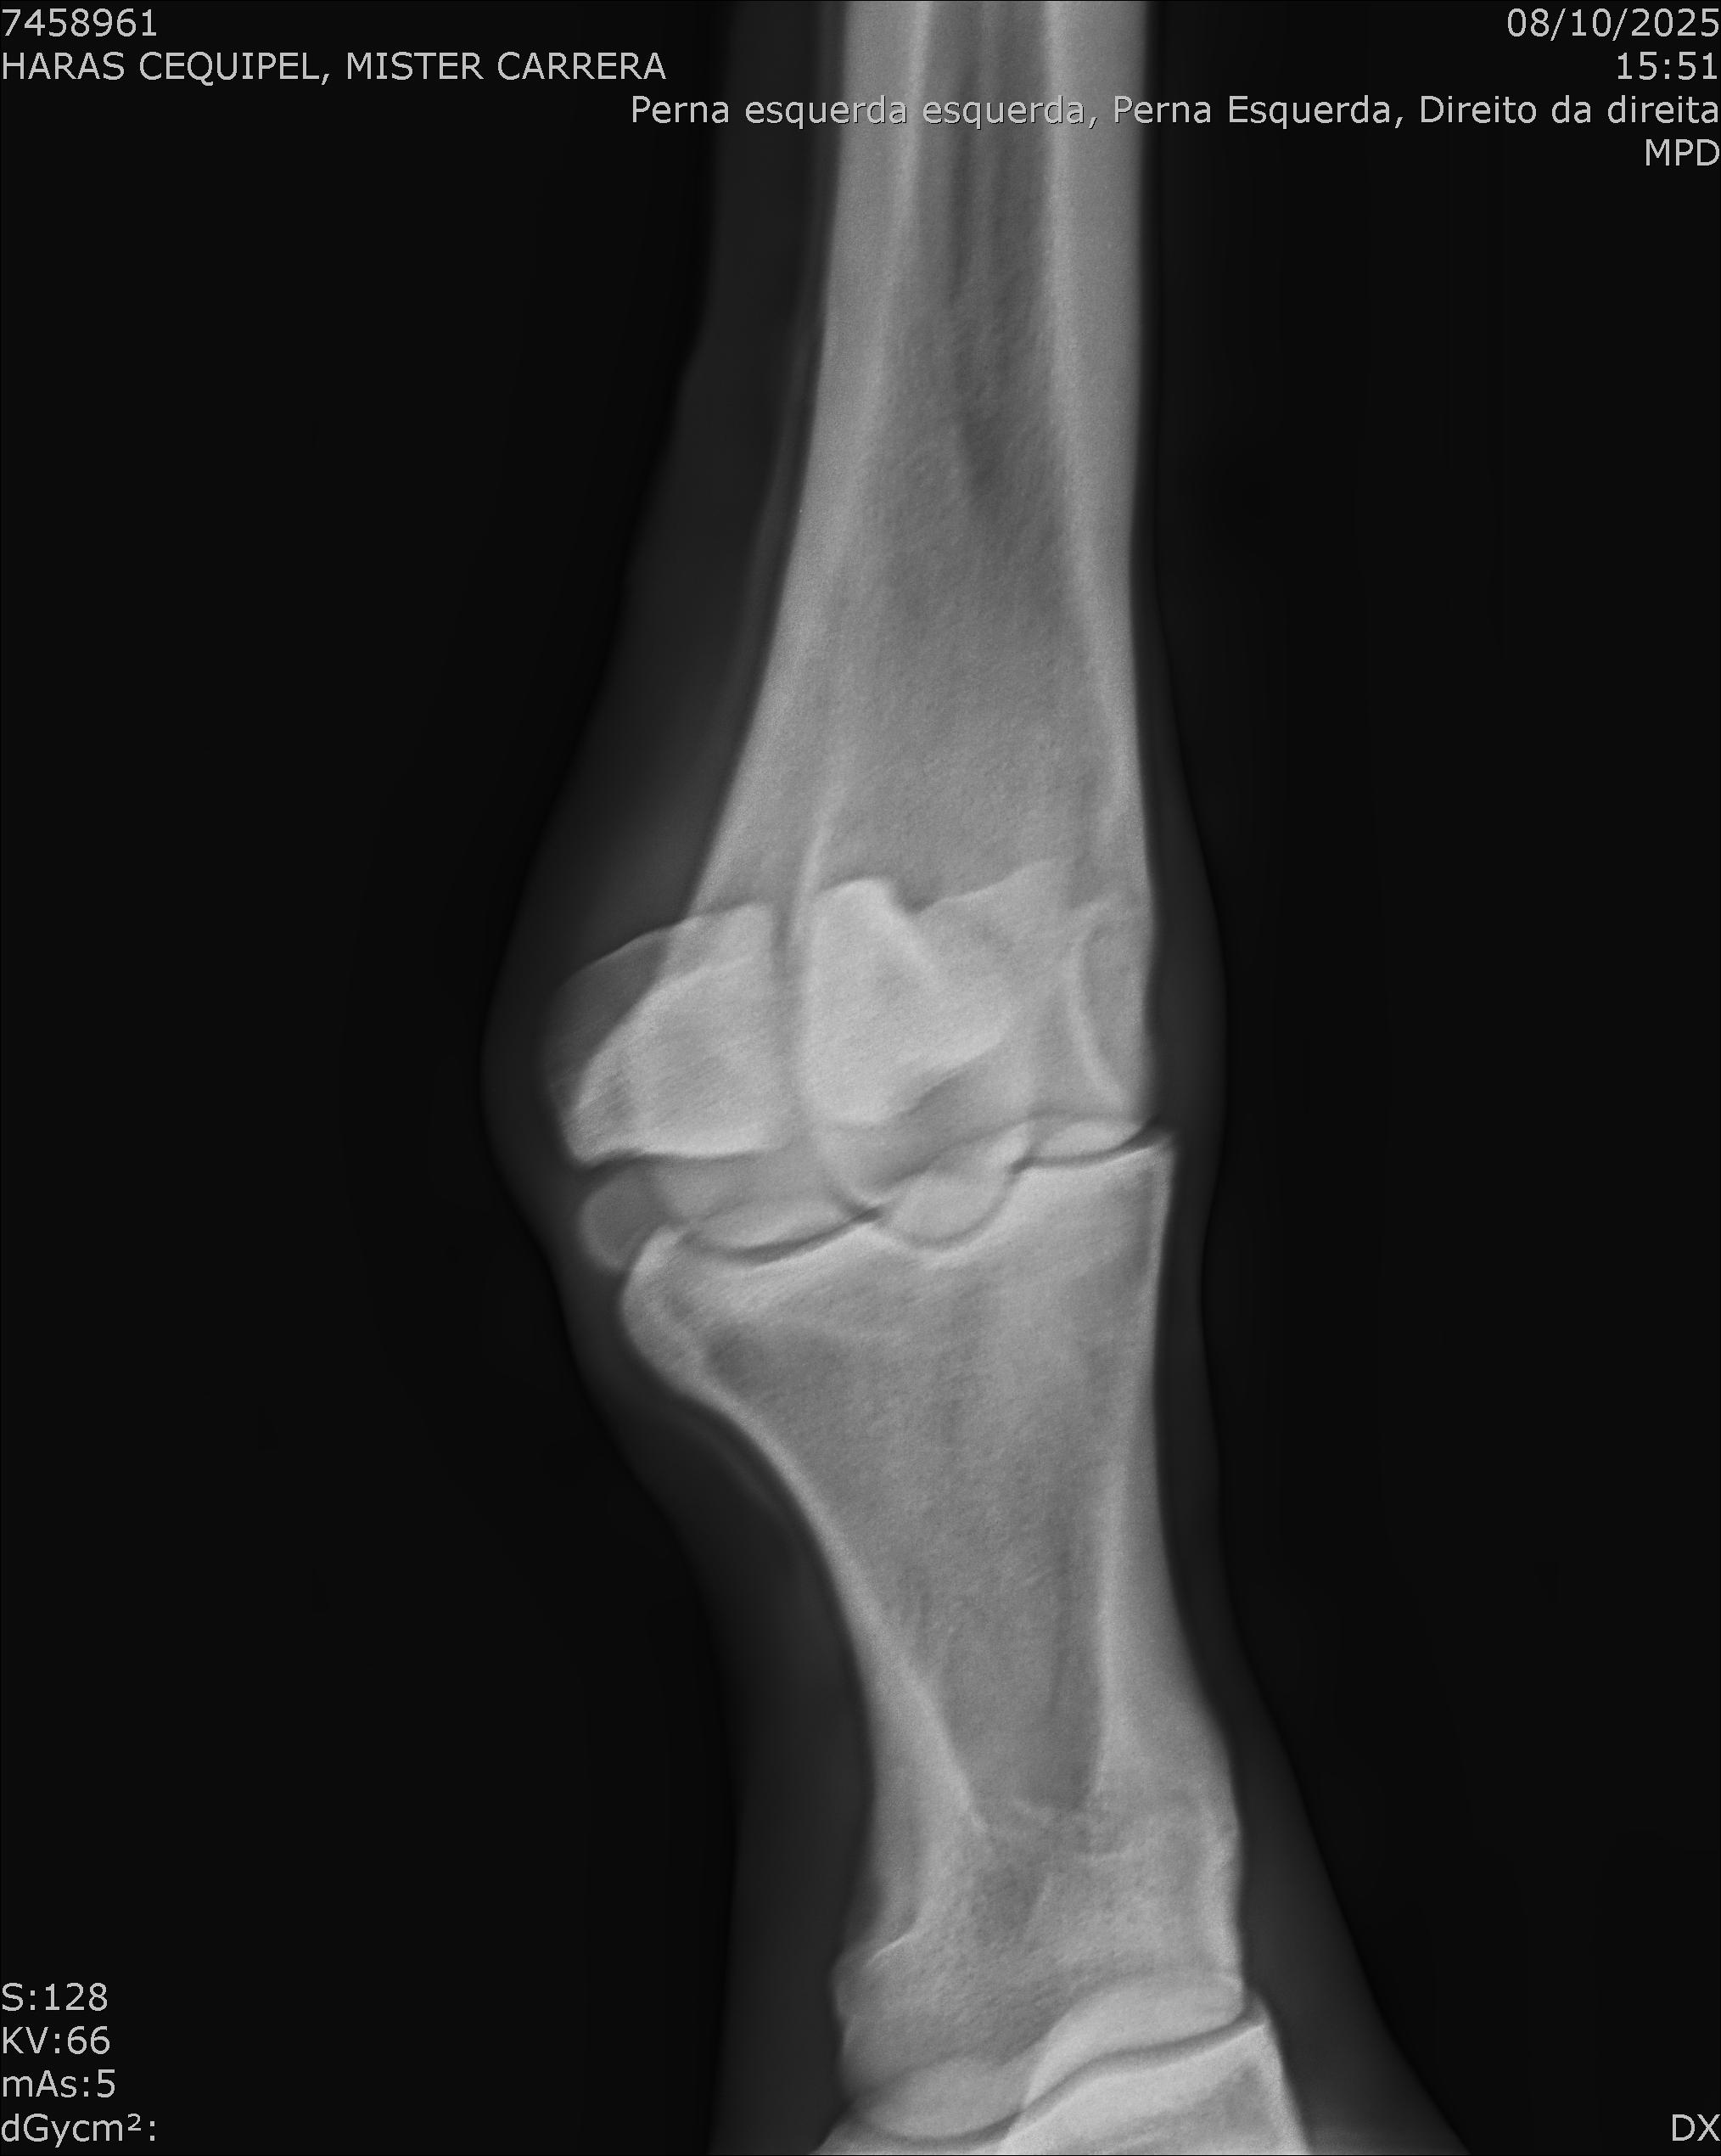

:: RAIOS-X DO LOTE